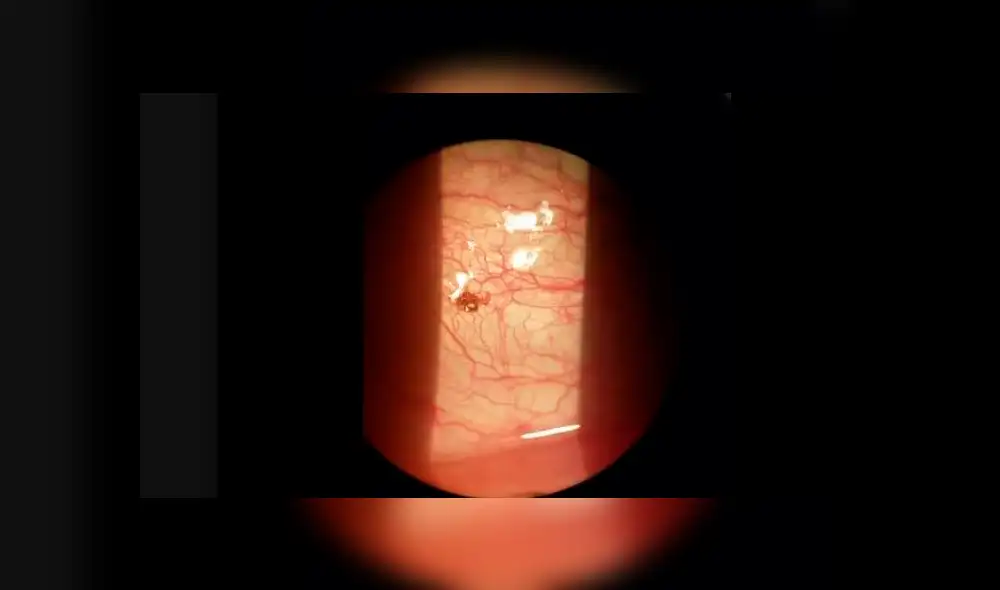

Chris Prater, el protagonista de esta historia compartida en Facebook, no quiso ir al oftalmólogo porque creía que el dolor desaparecería, sin embargo, al continuar con las molestias, acudió al doctor, en donde se le halló un horrible bicho viviendo en su órgano.

“Fue entonces cuando me asusté un poco”, contó Prater. “Me incliné, lo miré y le pregunté si estaba bromeando y dijo: ‘No, tienes una garrapata'”, declaró.

El experto anestesió a Prater y usó unas pinzas para retirar a la garrapata Una vez que la agarró y la quitó, la garrapata hizo un sonido como un pequeño estallido cuando salió de mi ojo", aseguró el hombre.